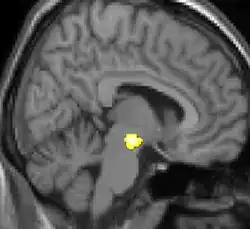

![]() |

| Tomografia PET mostrando áreas ativadas na dor. | ||

| VBM mostrando diferenças estruturais entre cérebros | ||

As reais causas da cefaleia em salvas (CES) ainda são desconhecidas, mas, de acordo com alguns estudos, os padrões das crises, as influências pelo horário do dia e as estações sugerem que o relógio biológico do corpo está envolvido. Nos seres humanos, o relógio biológico está situado no hipotálamo. Durante um ataque, o hipotálamo libera substâncias químicas que podem estimular as células nervosas no cérebro, causando dor e outros sintomas. A hiperatividade nervosa também pode causar um alargamento (vasodilatação) das artérias no lado afetado do cérebro. Uma teoria é que as dores são causadas por um alargamento dos vasos sanguíneos, que pressionam sobre os tecidos nervosos próximos, causando dor.[5] Exames de ressonância magnética sugerem dilatação da artéria oftálmica durante uma crise de cefaleia, enquanto a tomografia por emissão de pósitrons (PET) revela atividade dentro do seio cavernoso. Em alguns casos, existem fatores genéticos também, pois é mais comum entre familiares.[6]